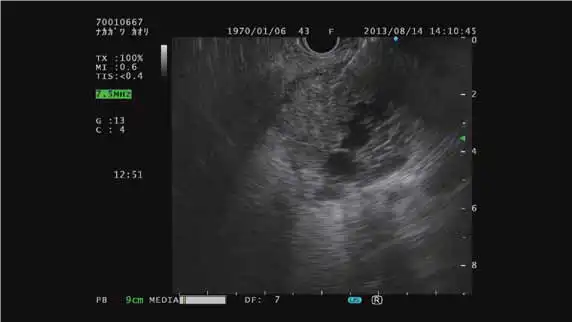

与电子环扫超声内镜配套使用

COLOR FLOW模式 THE-R模式 ELST模式